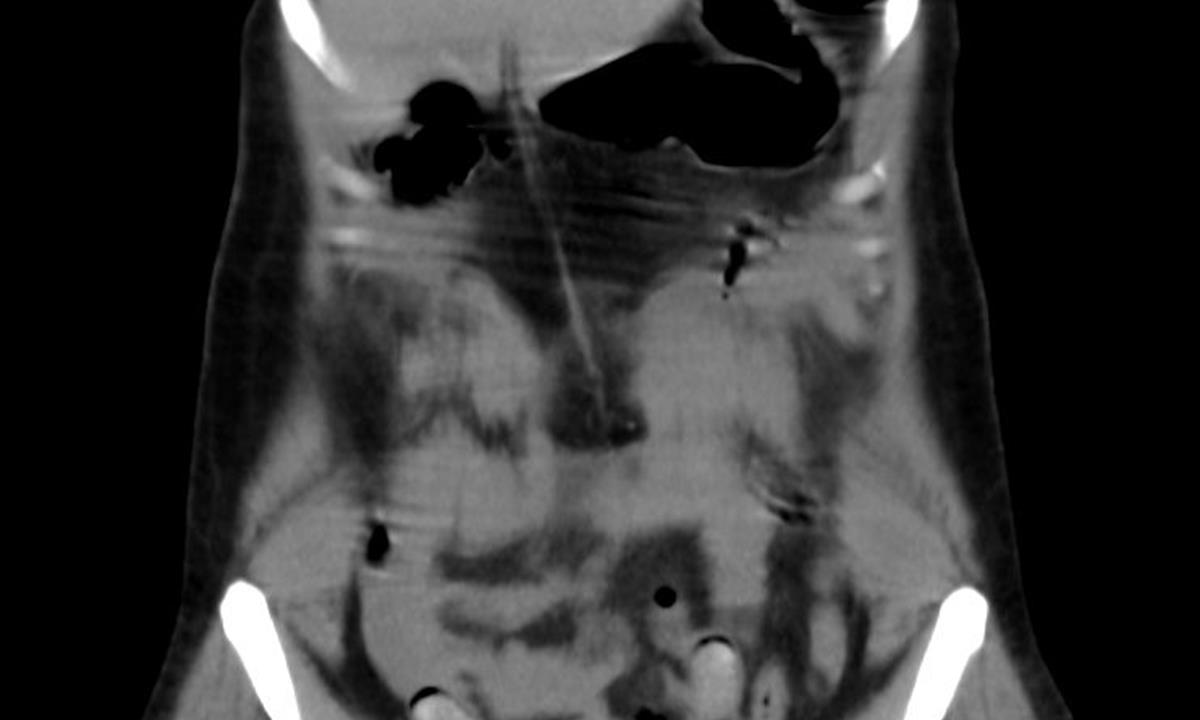

O víkendu odhalili celníci na pražském letišti Václava Havla v Ruzyni polykače kokainu. Jednalo se o 35letou cizinku, která postupně vyloučila 11 kapslí obsahujících drogy. Cizinka cestovala na pravidelné lince Madrid-Praha.

Ke kontrole byla polykačka celníky vytipována na základě provedené rizikové analýzy daného letu. Prvotní podezření na pašování drog celníkům potvrdily kontrolní stěry z rukou pašeračky.

Postupně z těla pašeračky vyšlo 11 kontejnerků naplněných bílým práškem. Jeden o váze 116,3 gramů byl ukryt v pohlavním ústrojí ženy. Chemická látka při provedení detekční zkoušky pozitivně reagovala jako kokain. Celková hmotnost všech kapslí včetně drogy je více než 230 gramů. Určení vlastní hmotnosti a druhu zajištěné drogy je předmětem další odborné expertízy. Podle zkušeností celníků se s největší pravděpodobností jedná o velmi koncentrovaný kokain. Zda byla droga určena na český trh nebo k distribuci v jiné zemi, je předmětem dalšího šetření.